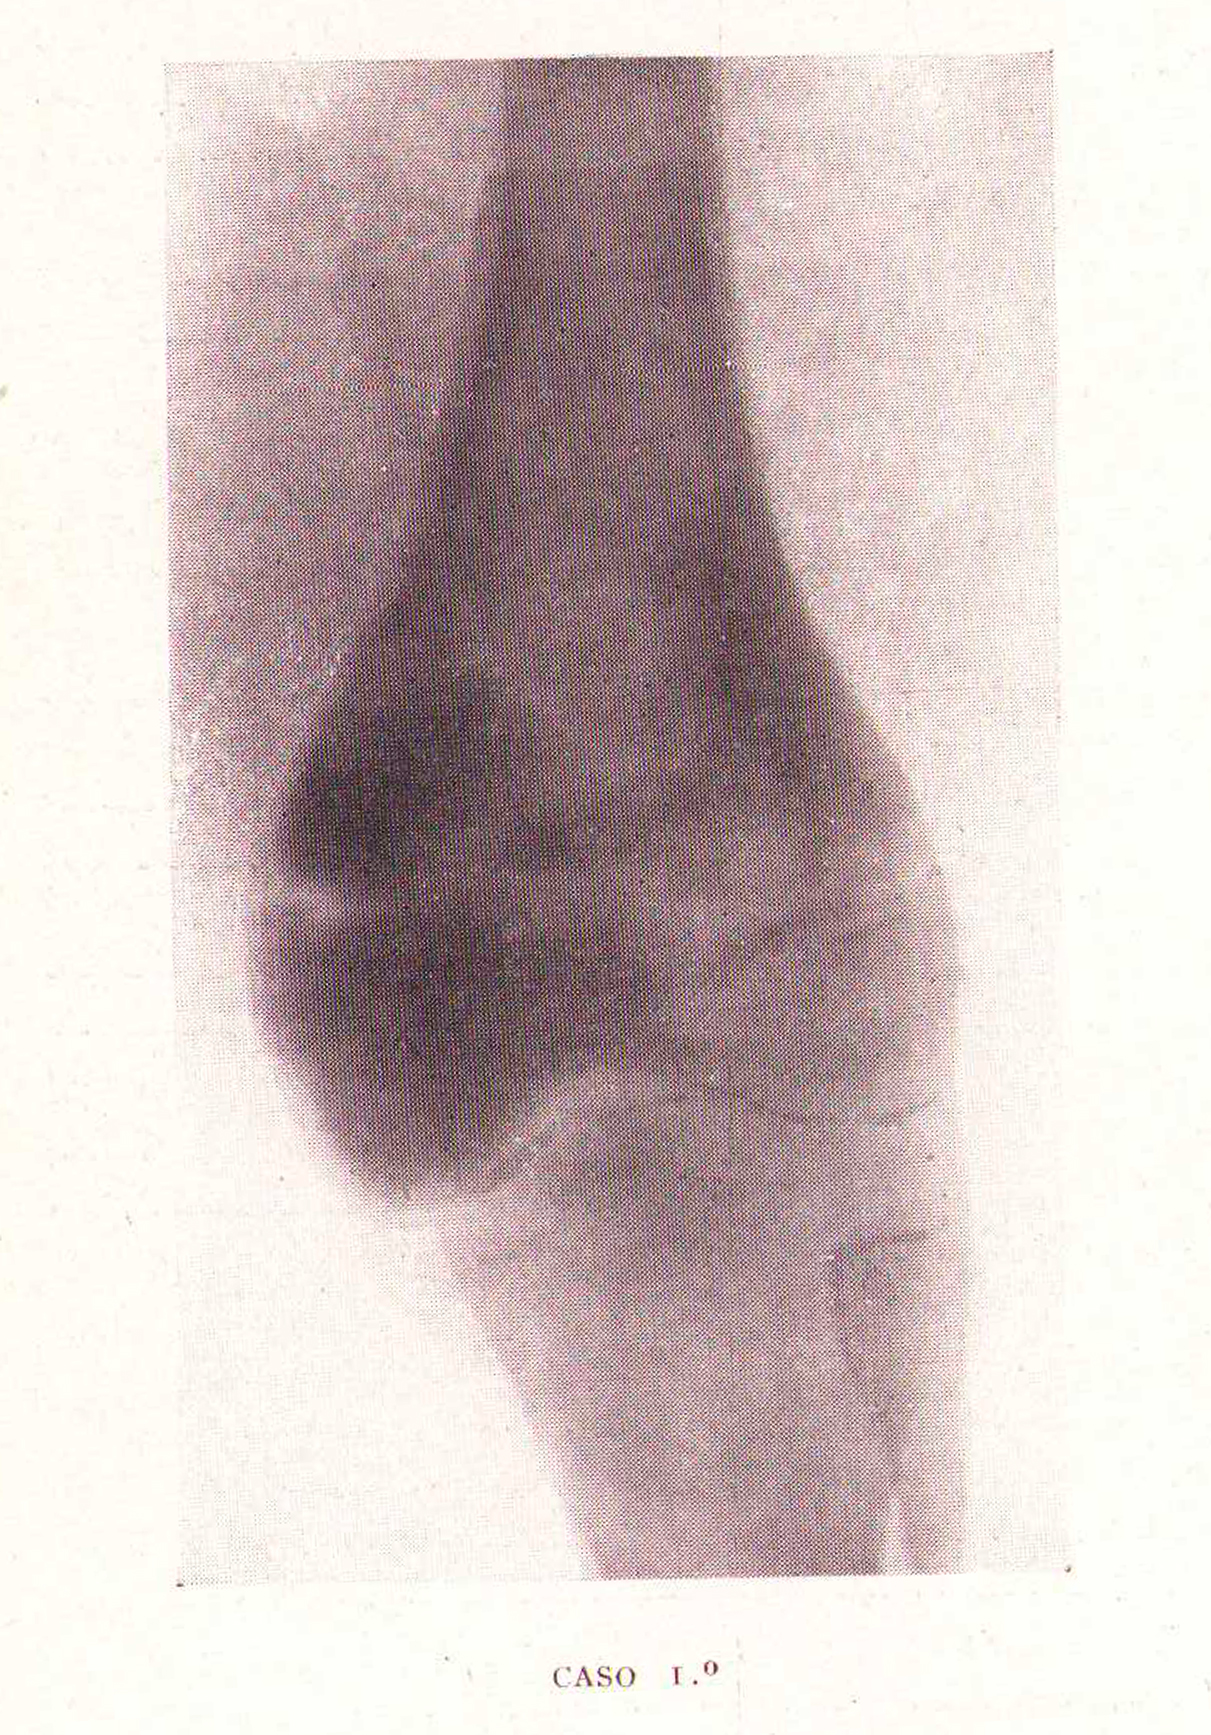

Caso 1º, Varón, Fémur ocupado por una tumoración

Revista Española de ciencias médicas, Clínica y laboratorio, Tomo XXXV, 1943.